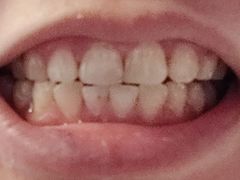

• 岳辰齿科(浦东长泰店)

• -岳辰齿科(浦东长泰店)

灼灼其桦_Lisa | 23-10-31